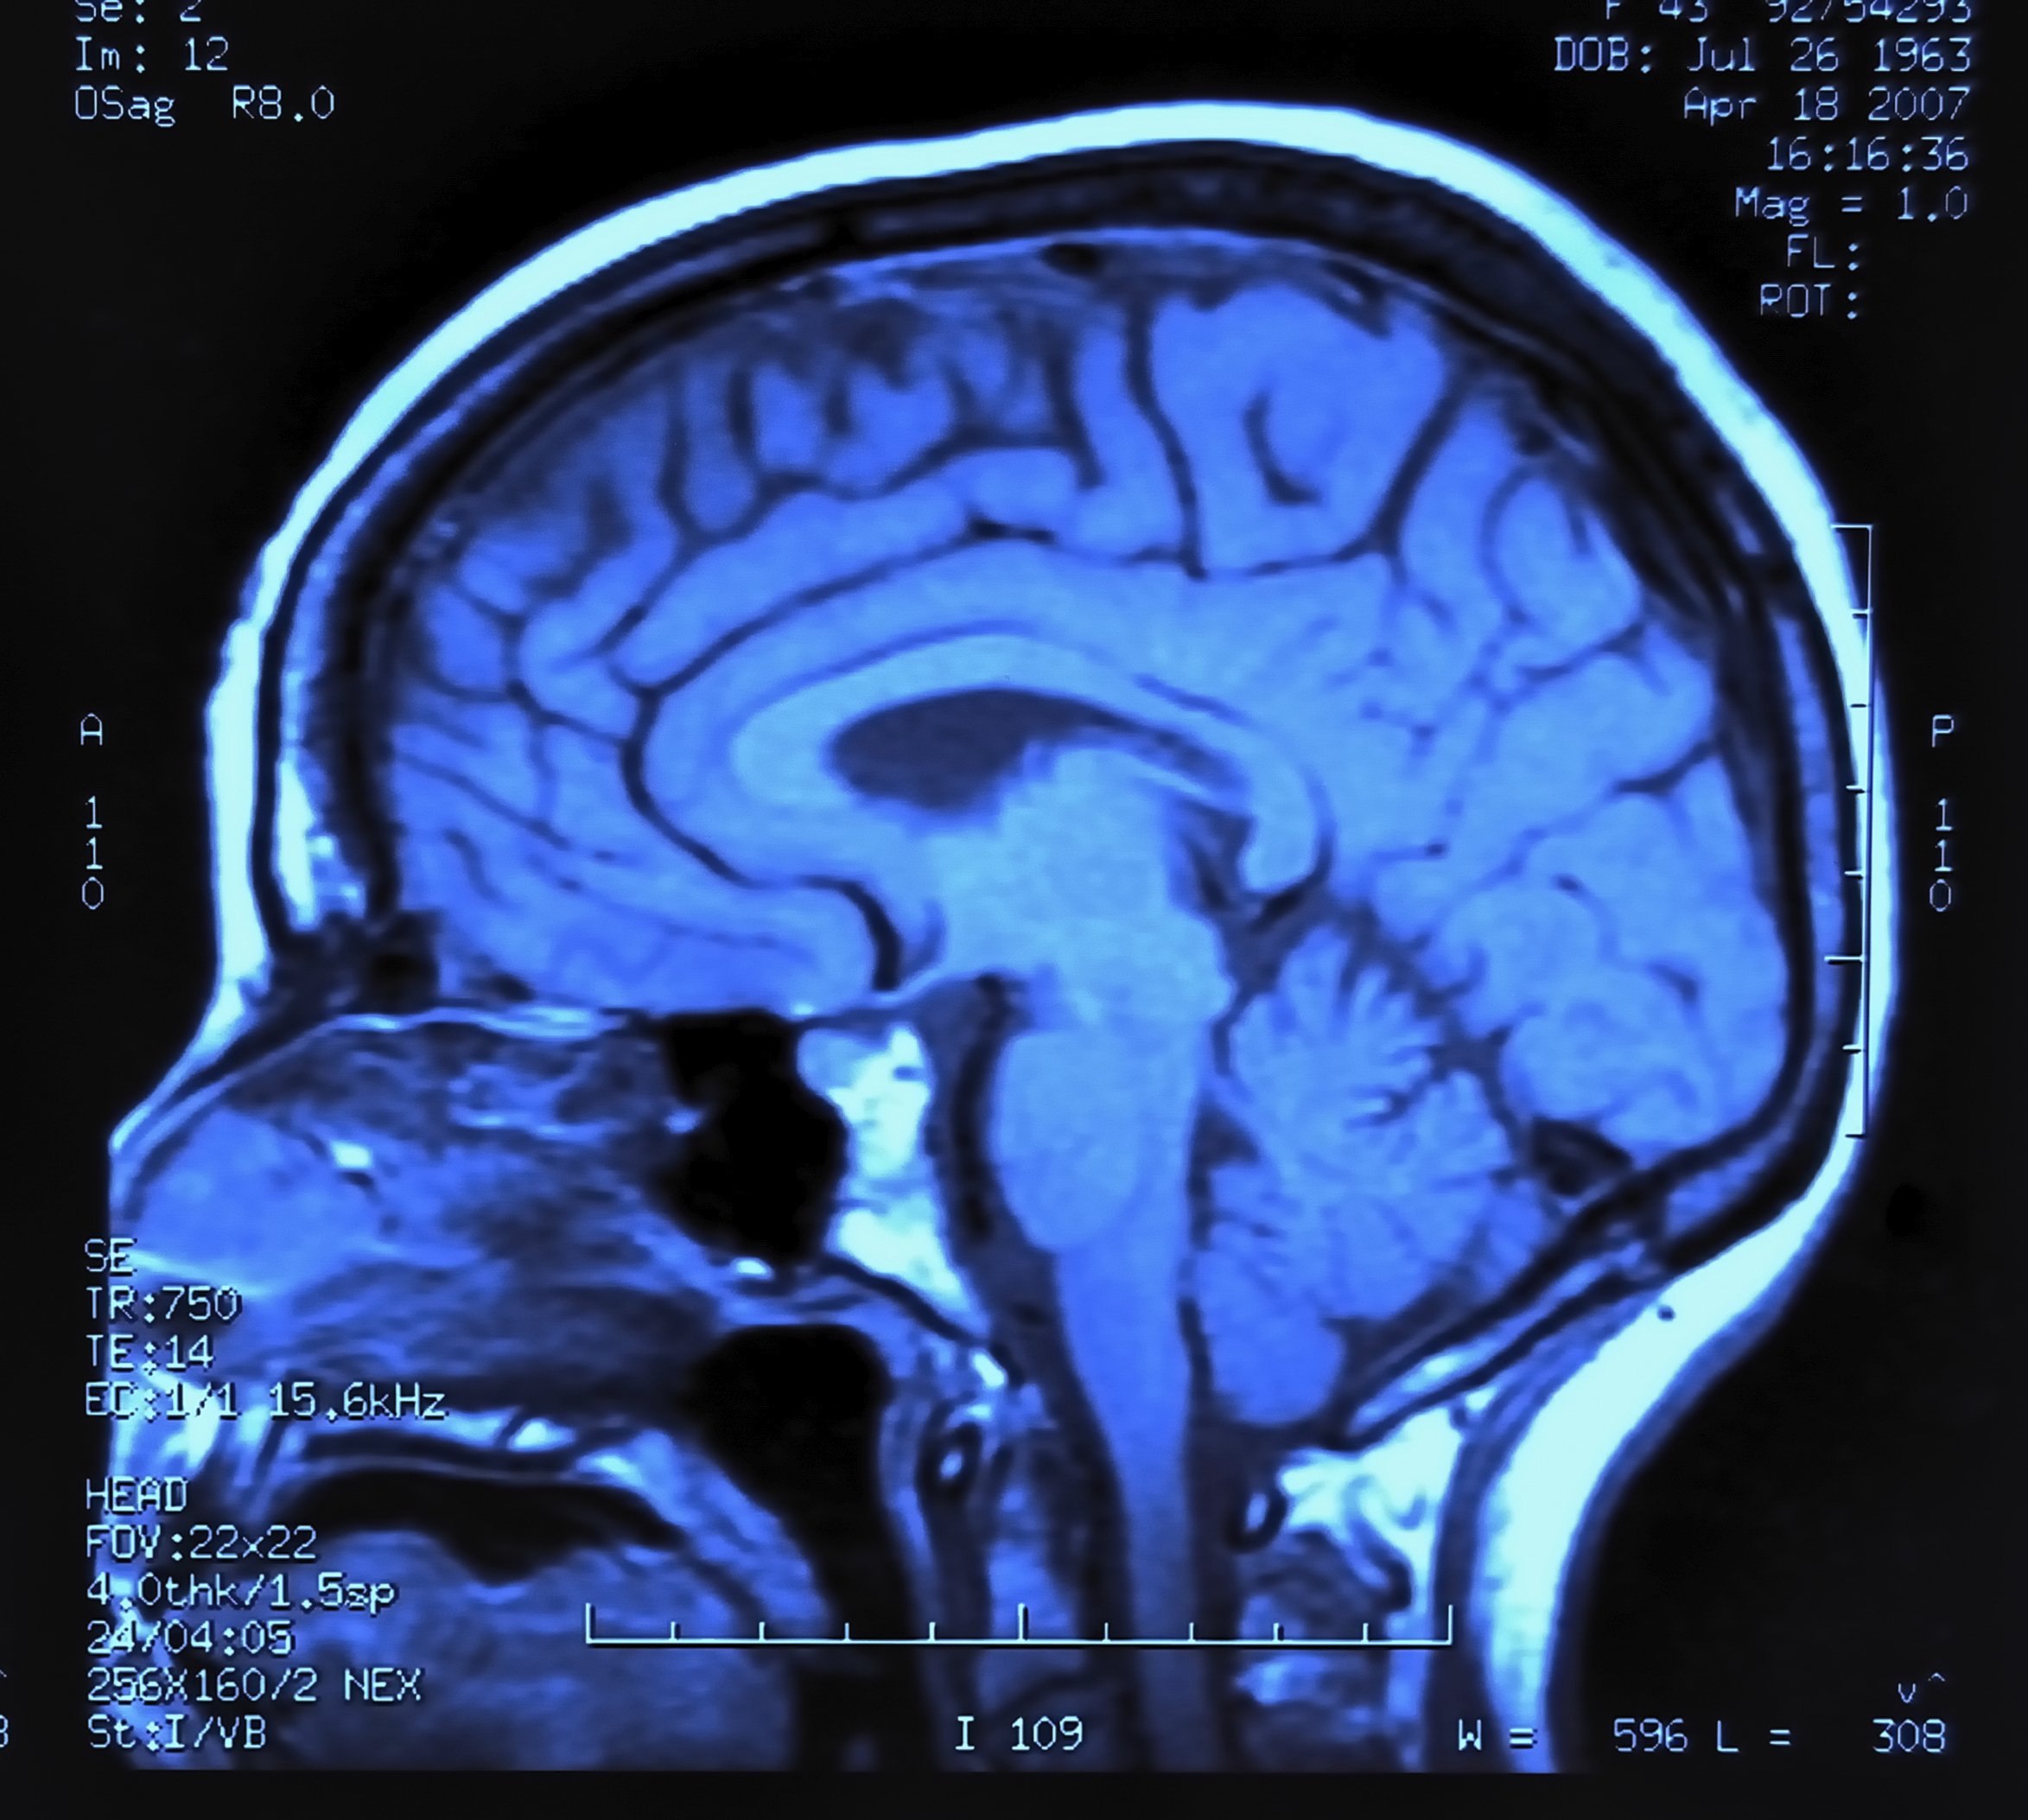

Prescription drugs used in the treatment of brain disorders, including Alzheimer’s disease, attention deficit hyperactivity disorder (ADHD) and narcolepsy, boost acetylcholine in the brain, improving alertness and attention.